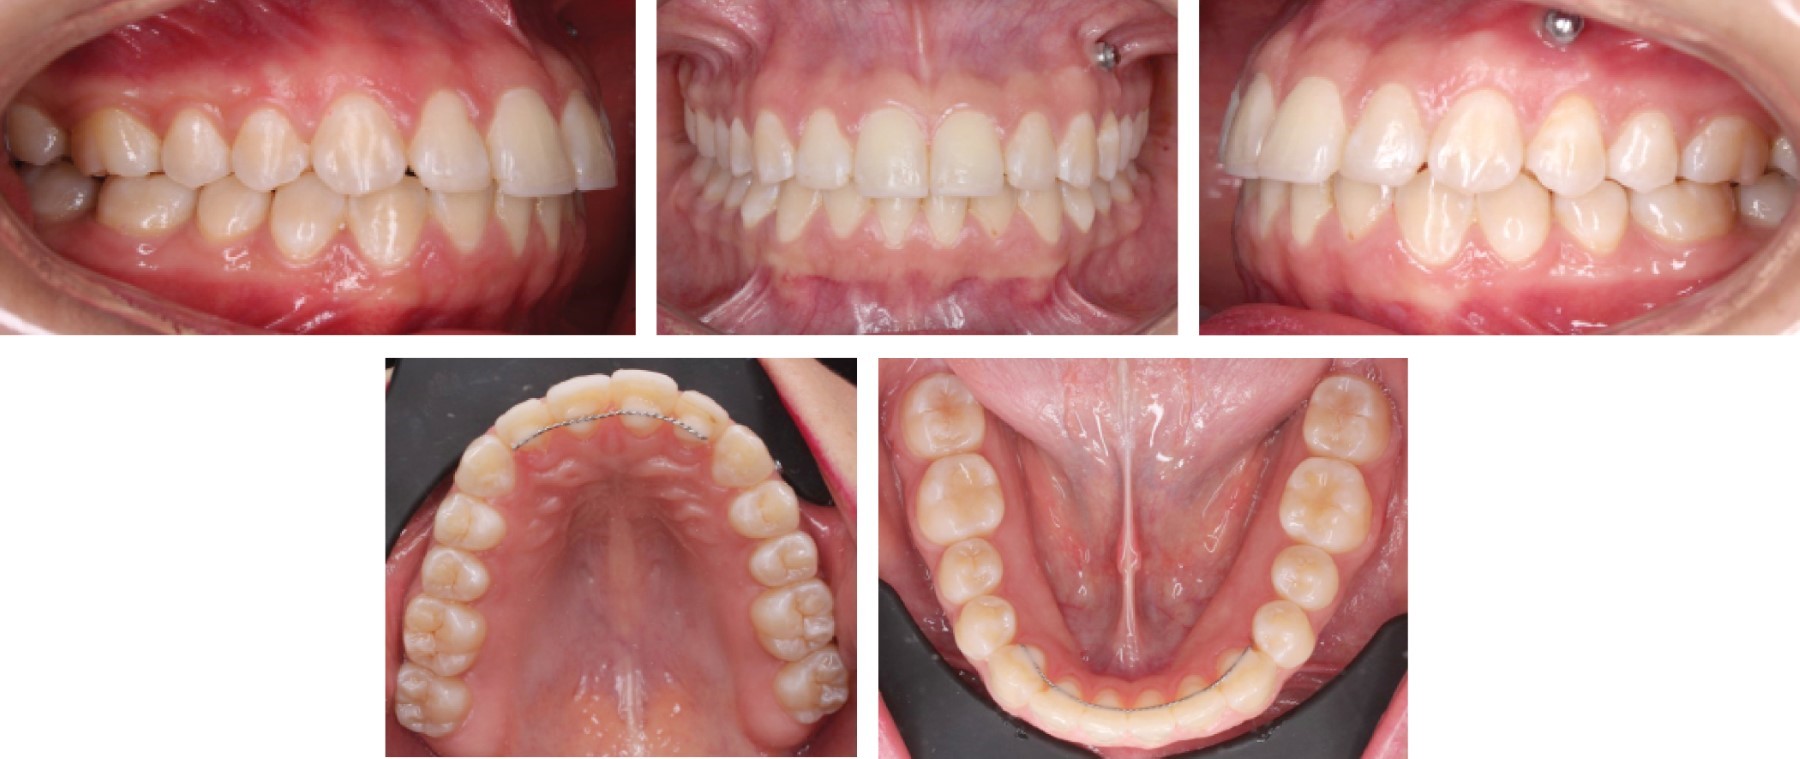

Paciente femenino de 24 años que acude a Clínica de Ortodoncia en la Escuela Nacional de Estudios Superiores Unidad León para corregir un canteamiento evidente. No presenta enfermedades crónicas ni datos patológicos que interfieran con el tratamiento. Diagnóstico: clase I esquelético biprotrusiva con crecimiento neutro, facialmente es una paciente braquifacial con perfil recto y retroquelia, se observó asimetría facial en la comparación del lado izquierdo y derecho. Incisivos superiores proinclinados, giroversiones, clase molar III derecha e izquierda, clase I canina bilateral, línea media desviada y plano maxilar canteado donde se observa que se necesita una intrusión de 5 mm para corregirlo (Figuras 1, 2 y 3).

Figura 1

Figura 2